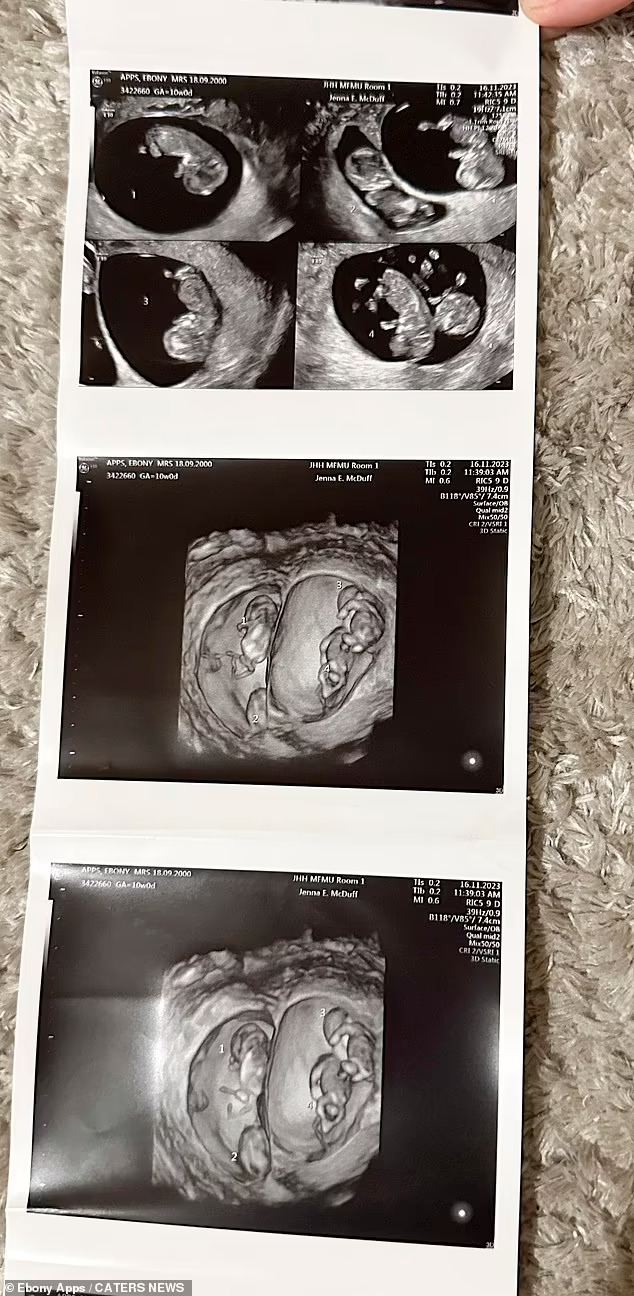

„Потоа, на нашето второ скенирање, ни беше кажано дека имаме четворки кои беа две групи идентични близнаци“.

Бременоста на идната мајка е поретка од четворократна бременост, бидејќи таа носи две групи идентични близнаци.

„Нашиот лекар ни кажа дека четворната бременост е околу една од 700.000, а да се биде бремена со две групи идентични близнаци е уште поретка. Една медицинска сестра рече дека во своето 30-годишно искуство никогаш не видела дека се случило ова“.

Веројатноста да се има две групи идентични близнаци во четирикратна бременост е еден на 70 милиони.